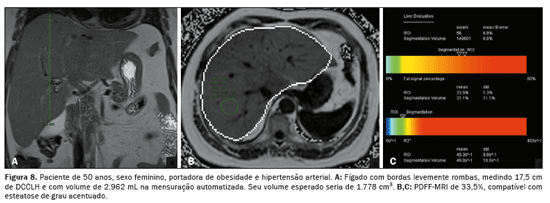

A associação, tanto do DCCLH e a PDFF-MRI (rs = 0,474;

p < 0,001) quanto da Voe e a PDFF-MRI (rs = 0,568;

p < 0,001), apresentou correlação estatisticamente significante, refletindo os resultados das análises anteriores (Figura 5). A relação entre o acúmulo de gordura e o aumento do volume hepático está exemplificada nas Figuras 6, 7 e 8.